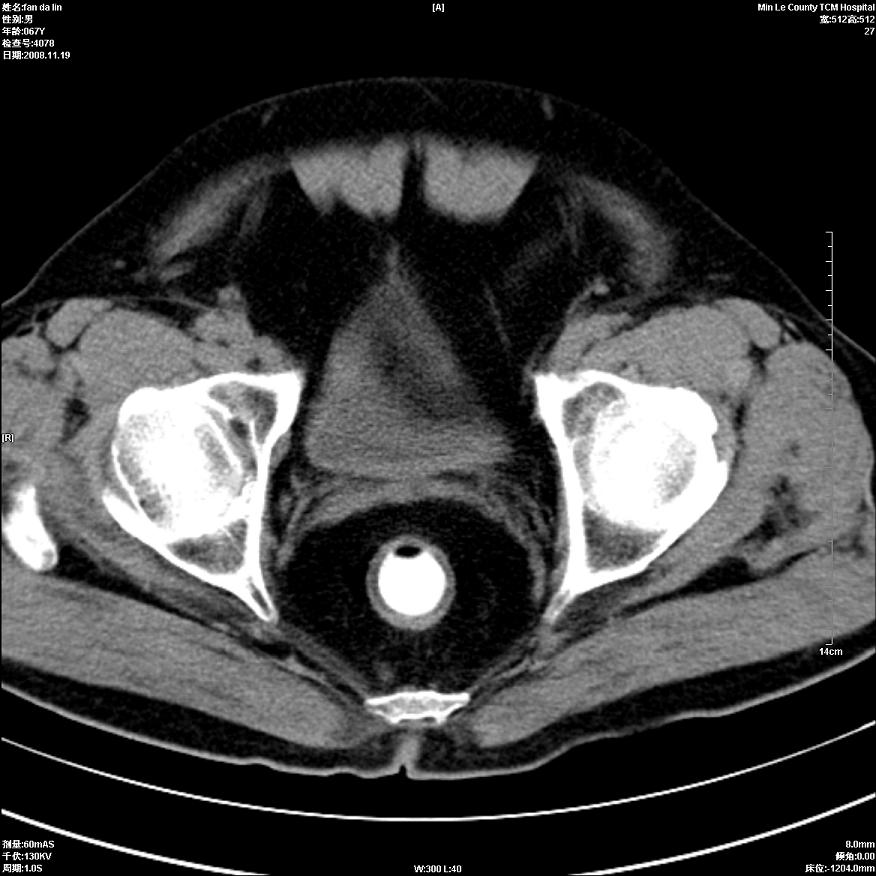

标题: CT16698:M67Y,看看直肠下端是不是病变 [打印本页]

标题: CT16698:M67Y,看看直肠下端是不是病变

粘膜皱壁,不除外内痔

直肠及乙状结肠管壁均增厚,考虑炎症.

直乙交界处肠壁不规则增厚,还是做个肠镜吧